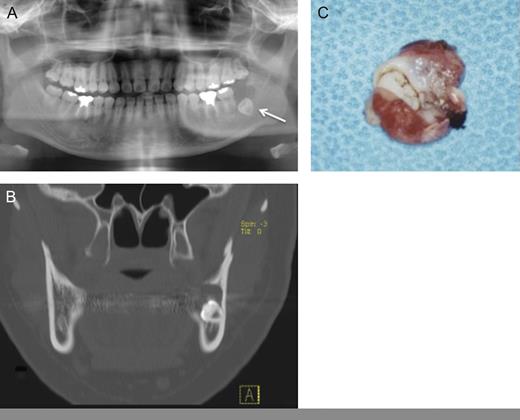

In 2009, a 26-year-old Japanese female patient was referred to our clinic, presenting with radiolucent cystic lesion in the left mandibular region. On oral examination, no swelling appeared to gingiva of the lower left second molar region. Neither paresthesia of the mental region nor palpable lymphadenopathy was observed. Panoramic radiography showed a radiolucent cystic lesion measuring 15 mm in diameter with impacted wisdom tooth (Fig. 1A). CT revealed a cystic lesion surrounding the crown of the wisdom tooth (Fig. 1B). Under clinical diagnosis of a dentigerous cyst, enucleation of the cystic lesion and removal of the wisdom tooth were performed (Fig. 1C). Histopathogical diagnosis was unicystic ameloblastoma (Fig. 2A and B). The postoperative course was uneventful.

(A) Panoramic radiography: a cystic lesion with wisdom tooth was seen in the left mandibular region. (B) CT showed a cystic lesion with bone destruction. (C) Gross appearance of surgical specimen showed like dentigerous cyst.